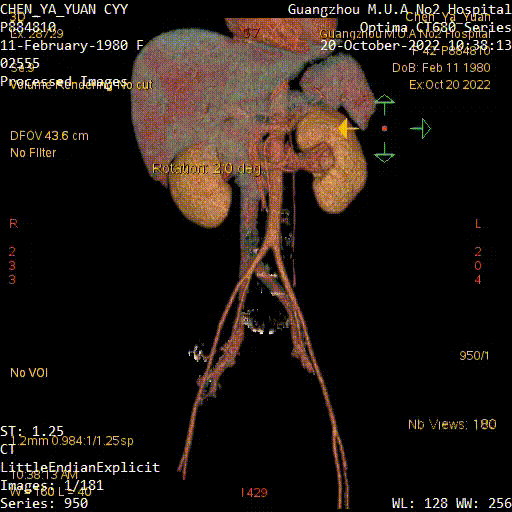

Case 3

男性,39岁

因“下腔静脉滤器留置10月”入院

患者10月前因“头颅外伤后右下肢肿胀”在外院行下腔静脉滤器植入术,2月前外院腔内回收滤器失败

查体:双下肢皮温暖,无肿胀,非凹陷性,双股动脉、腘动脉、足背动脉搏动可及。

入院彩超:下腔静脉及双下肢静脉无血栓

全腹CT及增强:下腔静脉滤器留置,无血栓

图为:入院全腹部CT及增强扫描